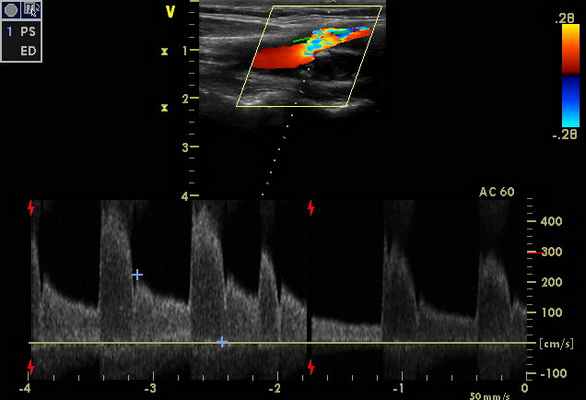

Признаки стенозов в V 2 сегментах позвоночных артерий с обеих сторон - по спектральным характеристикам - 75-85%, (правая ПА - на рис. 3). На рис. 4 – признаки субокклюзии – окклюзии ОСА слева (состояние после стентирования и эндартерэктомии - 2011 г.).

При транскраниальном исследовании - признаки коллатерального кровотока (рис. 6), с признаками повышение ЛСК по ЗМА с обеих сторон, в т. ч. на фоне стенозирования от 50% (рис. 5 - ЗМА справа), с регистрацией ретроградного кровотока по обеим глазным артериям (рис. 7 - правая ГА).